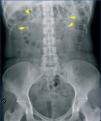

We treated a 28-year old pregnant woman (7 weeks gestation) that sought emergency treatment for intense weakness with vomiting and abdominal pain. She had a history of rhabdomyolysis secondary to severe hypokalaemia of an unknown cause, bilateral nephrocalcinosis, and nephrolithiasis (Figure 1). We reviewed the patient’s previous laboratory results and observed that she had hyperchloremic metabolic acidosis and hypokalaemia with persistently alkaline urine pH with several years’ evolution. Upon arrival in the emergency room, she had: AHT: 103/71mm Hg, HR: 78 systoles, deep abdominal palpation produced pain in the left hypochondria and fossa, with positive left renal percussion.

Figure 1. Simple abdominal x-ray